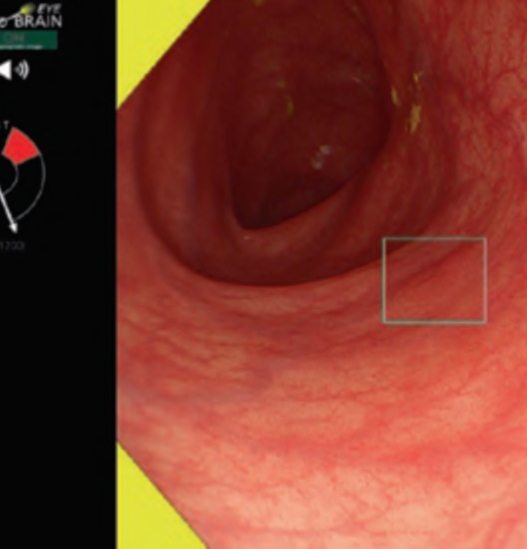

The working group members carried out a systematic review of the English literature to determine widely accepted diagnostic systems. Consequently, the best-accepted diagnostic system was proven to be the VS classification system. Based on this system, MESDA-G was constructed using an evidence-based approach (. Figs. 3, 4, 5, and 6) [2]. First, lesions suspicious for EGC should be detected by careful inspection using conventional white-light endoscopy. Subsequently, magnified observations should be performed. Owing to the high sensitivity of the demarcation line [8], if it is absent, the suspicious lesion is diagnosed as noncancerous (. Fig. 4a, b). However, if the demarcation line is present, further assessment is required to determine the presence of an irregular MV or MS pattern. If an irregular MV and/or MS pattern is detected, the suspicious lesion is diagnosed as cancerous (. Fig. 6a, b) [1, 5, 6, 8]. If both the irregular MV and MS patterns are absent, the tumor is diagnosed as noncancerous (. Fig. 5a, b) [1, 5, 6, 8].